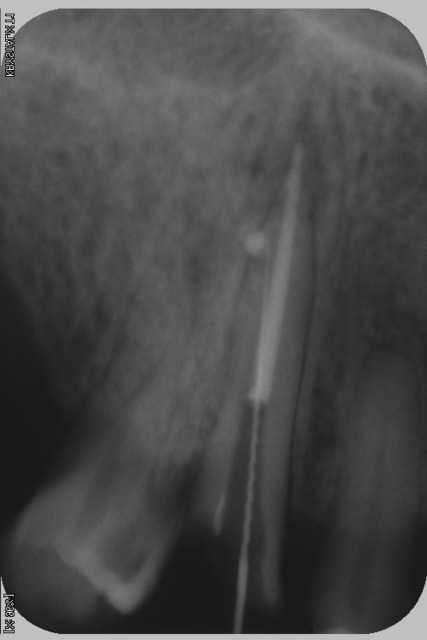

voila la radio dit tout

c'etait encours de preparation du logement du tenon fibré

patiente a ressenti une douleur vive lors de l'irrigation

il me semble que de manière concomitante, le péri apex n'était pas clair non plus DONC PRONOSTIC RESERVE pour la dent..

( élargissement péri apical, dépassement maitre cône, pârodontite apicale aigue/chronique résiduelle? )

J'ai pas l'impression vu ta dépose de gutta que tu te sois raté dans la prépa du tenon. Ce serait pas plutôt une fracture?

L'image radio circulaire de ciment était elle présente avant de commencer ta désobturation ?

Sinon je pense aussi à une fracture, la paroi étant très fine. Il faudrait savoir quel diamètre de foret tu as utilisé.

Je crois que tu as eu de la chance au final,et que le souci d'aujourd'hui évite à ta patiente d'investir sur une dent qu'elle n'aurait peut-être pas gardée très longtemps.

Ça sent le davier ta radio ........

et la dent 14 comment est-elle cliniquement...

à la radio semble y avoir 3 racines...